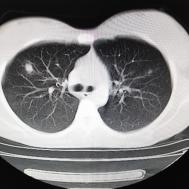

性别:女,年龄:26岁,低热,轻微胸痛,支原体阳性

[影像描述]

两肺内及胸膜下多发斑片状高密度影,部分病灶密度较淡,部分实变,边缘可见渗出改变。